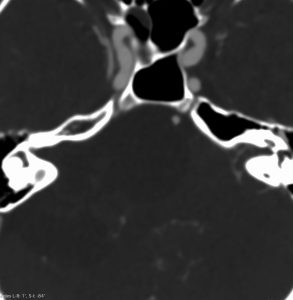

- 側頭骨内にあるものは,MRIよりCT (thin-slice bone-window)の方が正確に進展部位を把握することができます

側頭骨内(顔面神経垂直部)